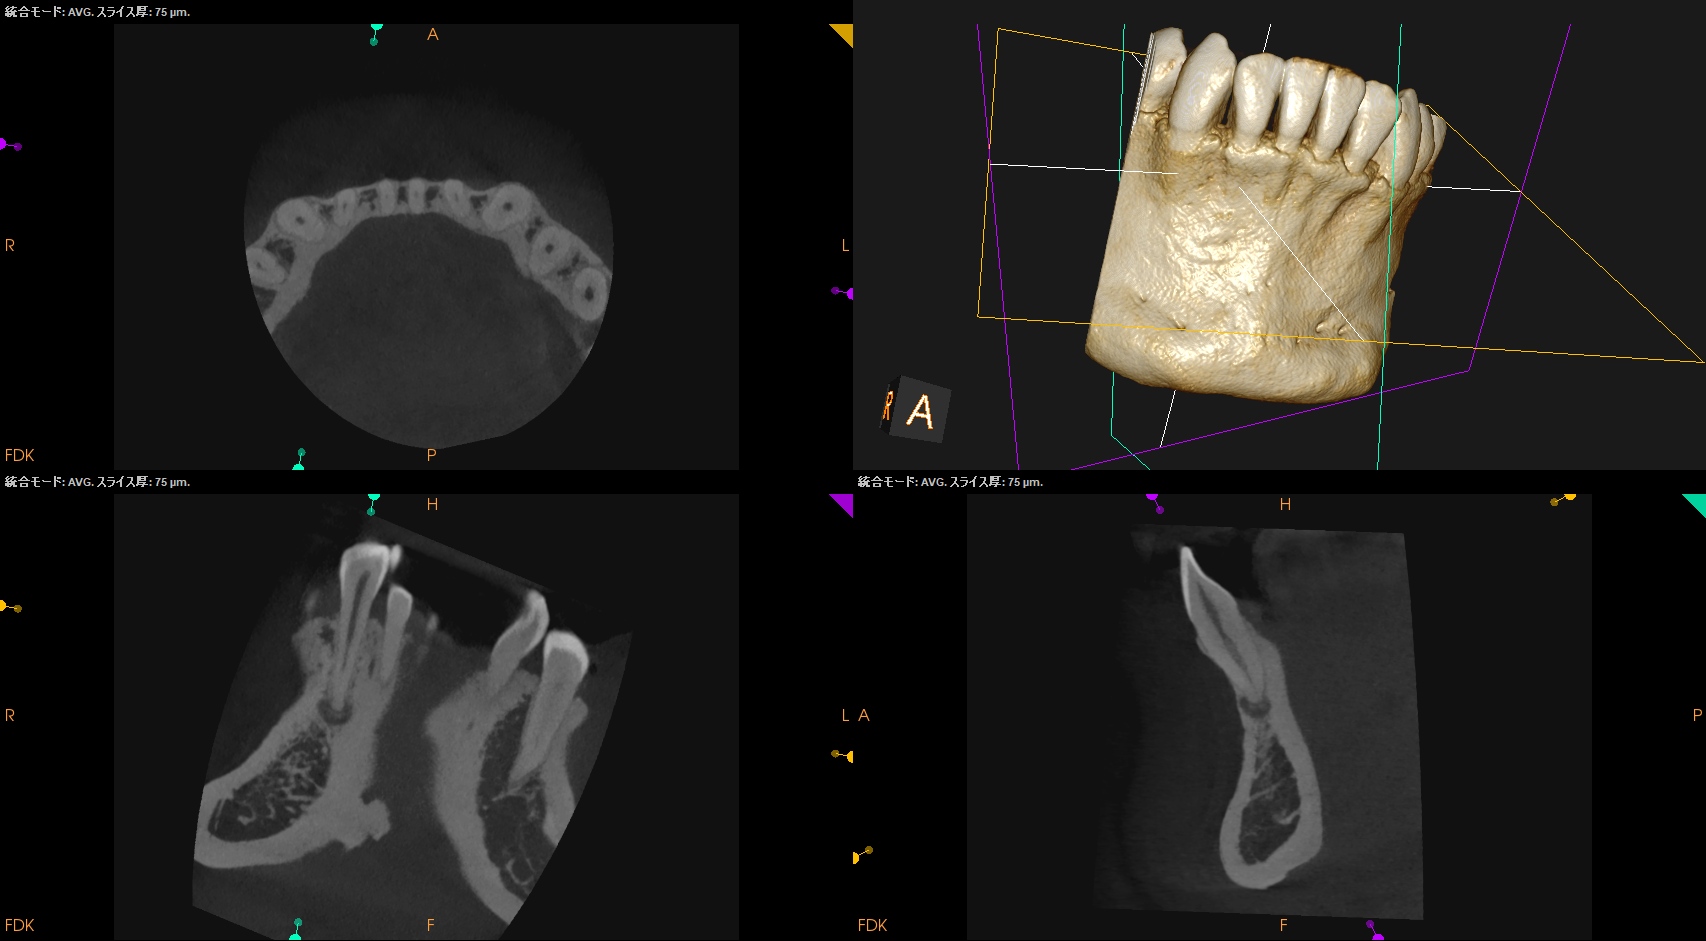

CBCT(2025.4.16)

全く治療歴がない歯の神経がなぜ失活したのだろうか?

患者さんには思い当たる節がないという。

多くの場合は外傷が関与していると言われる。

切端から3.5mmの部分を1.7mm削合すると露髄し、根管治療を行うための根管に到達できるだろう。

Pre-op Endo Diagnosis(2025.4.16)

Pulp Dx: Normal Pulp Tissues

Periapical Dx: Symptomatic apical periodontitis

Recommended Tx: RCT